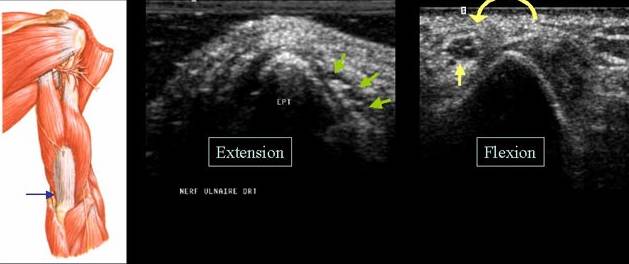

LUXATIA NERVULUI ULNAR

Nervul ulnar →

Sectiune transversala la nivelul santului epitrohleo olecranian

Nervul ulnar normal, cot in extensie →

Luxatie anterioara a nervului ulnar in flexia cotului →